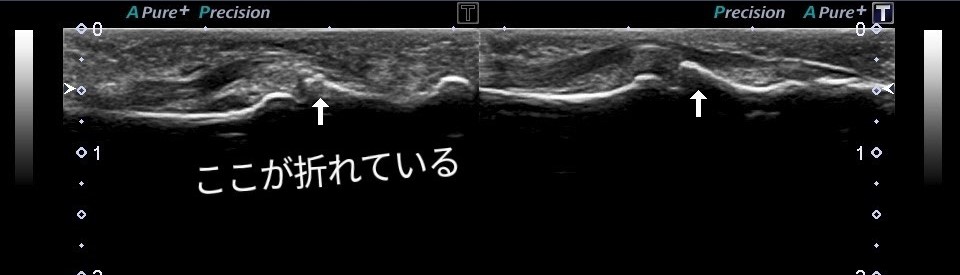

右手第5指損傷

エコー画像